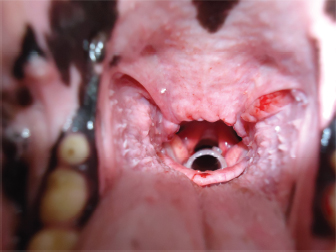

Once the stent is placed, titrated propofol IV is suspended and an oxygen face mask is again used until the dog recovers. It is necessary to check if the stent is correctly placed during this time. It might provoke a discrete cough immediately after waking, and no abnormal breathing sounds should be heard (no stridor nor noisy breathing) (Fig. 2). If there is any doubt about its placement, transoral laryngoscopy should be performed immediately.

Fig. 2. View of the laryngeal stent during a transoral laryngoscopy, after palatoplasty